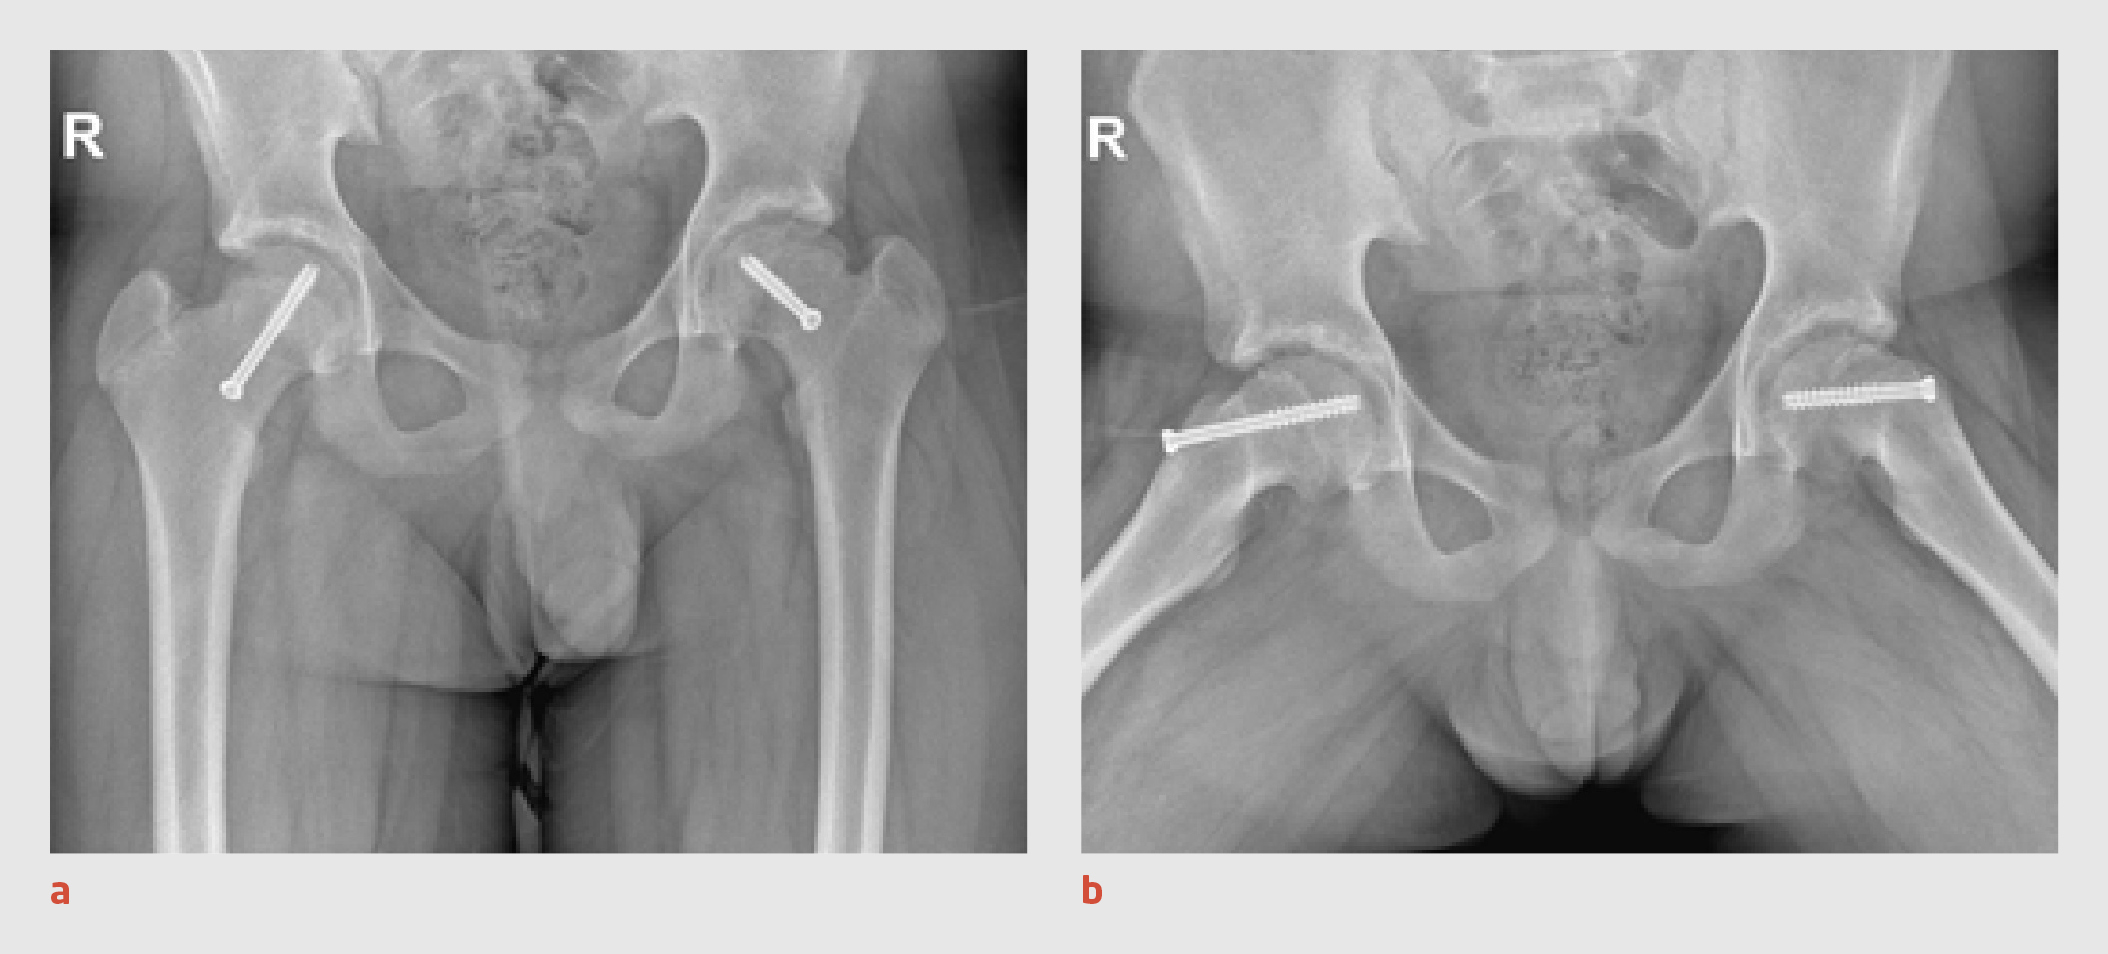

Wij schreven bedrust voor en opereerden patiënt de volgende dag, waarbij beiderzijds de epifyse van het caput ossis femoris werd gefixeerd middels percutane schroeven. Postoperatief moest patiënt 6 weken mobiliseren met krukken. Bij poliklinische controle na 1 jaar had patiënt een blokkadegevoel van de linker heup bij bukken en was er in beide heupen maximaal 10° endorotatie mogelijk. Het Drehmann-teken was beiderzijds aanwezig. Herhaalde röntgenopnames lieten de bekende standsafwijking van het caput ossis femoris zien, met een geringe sclerose van het acetabulum beiderzijds (figuur 5).

Figuur 5

Operatief gefixeerde epifyse van het caput ossis femoris

Figuur 5 | Operatief gefixeerde epifyse van het caput ossis femoris

Röntgenopnames van het bekken. (a) Anteroposterieure opname 1 jaar na schroeffixatie van het caput ossis femoris beiderzijds. (b) Gelijktijdige Lauenstein-opname.